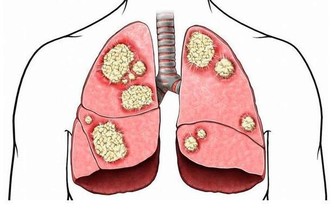

4.肺癌「免死金牌」————菠菜